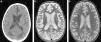

Al igual que el resto, la HSA traumática se observa con una hiperintensidad de señal del surco cortical afectado, principalmente en la secuencia FLAIR, y en forma menos sensible con baja señal en las GRE. Ambas secuencias resultan de suma utilidad en este tipo de cuadros (fig. 3).

Continuando con la HSA, la consulta por cefalea en estallido debe plantear la sospecha de una ruptura aneurismática como causante (fig. 4). En estos casos suele observarse contenido hemático en los espacios subaracnoideos corticales y en las cisternas, siendo más cuantioso el sangrado cerca del aneurisma roto. Si el cuadro es de mayor gravedad, la sangre puede volcarse al sistema ventricular.

La TC en corte axial detecta (a) una hiperdensidad en topografía silviana bilateral, con predominio del lado derecho (flechas), compatible con hemorragia subaracnoidea aguda. (b) La angio-TC (volume rendering) visualiza un aneurisma sacular de la arteria comunicante posterior derecha (cabezas de flecha), con irregularidad de la pared (sugestiva de ruptura).